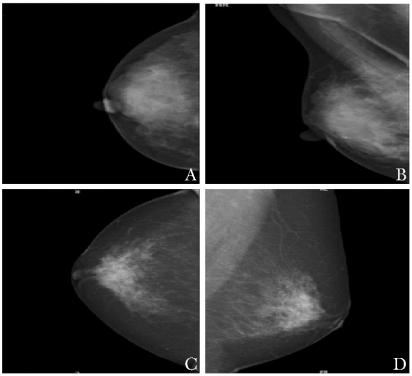

乳头溢液是乳腺疾病的常见症状,其发病率仅次于乳房肿块及乳房疼痛,占门诊患者主诉症状的4.8%~7.4%[1]。 乳头溢液又分为生理性和病理性两种。病理性乳头溢液的病因包括导管内乳头状瘤、乳腺腺病、导管扩张、乳腺癌等[2]。其中,导管内病变是造成乳头溢液的主要病因,溢液性状可分为血性和非血性,后者又包括浆液性、混浊黏液样等。 本文通过回顾性分析173例病理性乳头溢液患者的临床、病理特点及其诊治情况,以期发现病理性乳头溢液,特别是血性溢液是否存在特殊的临床病理特点,临床诊断方法能否为治疗提供充分依据,治疗及术后随访是否合理,从而为该病临床诊治提供依据。 1 资料与方法 1.1 临床资料 回顾性收集北京协和医院2015年1月至12月间住院并手术的病理性乳头溢液(血性溢液、黄色浆液性或混浊黏液样溢液)患者的临床、病理以及术后随访资料。 纳入标准: (1)非妊娠期、非哺乳期女性; (2)首发症状为自发性乳头溢液; (3)乳头溢液为血性溢液、黄色浆液性或混浊黏液样溢液; (4)术前体格检查,乳腺超声、钼靶等影像学检查,术后石蜡病理等资料齐全。 排除标准: (1)男性; (2)首发症状为乳房肿物; (3)乳汁样或无色透明样乳头溢液; (4)术前评估不完善; (5)于外院行手术治疗。 1.2 术前检查 所有患者术前均进行体格、超声及钼靶检查。体格检查主要记录乳头溢液单侧、双侧、单孔或多孔及是否合并可触及肿块。超声检查均于我院超声科进行,采用PHILIPS HD11XE超声机,探头采用L12-5,频率为5~12 MHz。患者仰卧位接受检查,主要记录乳房内是否存在低回声病变或导管内低/高回声。乳腺钼靶检查均于我院放射科进行,患者取立位,行常规乳腺头尾位及内外侧斜位检查。根据美国放射学乳腺影像报告和资料系统(BI-RADS)进行诊断,主要记录是否存在钙化及肿块。 1.3 手术方式 所有患者术中先采用美兰进行切口定位(图1A),然后行乳腺病变导管及相关腺叶切除术(图1B)。术中冰冻或石蜡病理结果回报为恶性病变的患者,进一步行保乳手术或乳房切除术,腋窝行前哨淋巴结切除术或腋窝淋巴结清扫术。 图1 乳腺病变导管及相关腺叶切除术 A.手术切口;B.切除的病变标本 1.4 病理检测 术后病理均采用HE染色。HE染色石蜡病理切片均由病理科医师根据2012版世界卫生组织乳腺肿瘤诊断标准进行诊断[3]。 1.5 术后其他治疗及随访 术后根据手术方式及病理结果,部分患者行化疗、放疗及内分泌治疗,所有患者均未行曲妥珠单克隆抗体靶向治疗。所有患者均采用电话随访方式进行术后随访。 1.6 统计学处理 采用SPSS 22.0统计学软件进行统计分析,符合正态分布的计量资料采用均数±标准差表示,非正态分布的计量资料以中位数(四分位数)表示,组间比较采用t检验或Mann-Whitney U检验;计数资料采用频数(率)表示,组间比较采用χ2检验或Fisher精确概率检验。以P<0.05为差异具有统计学意义。 2 结果 2.1 一般临床资料 共173例符合纳入和排除标准的患者入选本研究,均为女性,平均年龄(45.65±13.48)岁,中位病程3(1, 12)个月。其中血性溢液119例(68.8%,119/173),非血性浆液性溢液54例(31.2%,54/173);仅2例(1.2%,2/173)为多孔溢液,其余均为单孔溢液;168例(97.1%,168/173)为单侧乳头溢液,5例(2.9%,5/173)为双侧乳头溢液。 173例患者中,23例术前触诊可触及乳腺肿块,150例未及乳腺肿块;超声检查发现111例(64.2%,111/173)患者显示乳房低回声或导管内低/高回声(图2),62例未见异常;钼靶检查中,仅35例患者发现乳腺肿块影或钙化灶(图3),138例患者钼靶无异常。 图2 乳腺超声提示乳房内低回声(A)及导管扩张(B) 图3 乳腺钼靶提示合并钙化及肿块 A、C. 乳腺头尾位;B、D. 乳腺内外侧斜位 173例患者中,160例先行乳腺病变导管及相关腺叶切除,9例患者行乳腺肿物切除术+病变导管及相关腺叶切除术,4例患者仅行乳腺肿物切除术。根据术中冰冻或石蜡结果,27例患者诊断为乳腺癌,其中4例行包括乳头乳晕的中心象限局部扩大切除术,3例行中心象限局部扩大切除术+前哨淋巴结活检术,14例行乳腺单纯切除+前哨淋巴结活检术,1例仅行乳腺单纯切除术,5例行乳腺改良根治术。 术后石蜡病理回报:乳腺癌27例,其中浸润性癌6例,导管内癌19例,其他类型癌(黏液癌及神经内分泌癌)2例,行前哨淋巴结活检或腋窝淋巴结清扫术的患者,术后病理均未见淋巴结转移;不典型增生15例;良性病变以导管内乳头状瘤为主,共92例;其他良性病变包括乳腺腺病21例、纤维腺瘤4例、导管扩张14例(图4)。 图4 乳头溢液患者术后病理切片(HE,×100倍) A.乳腺导管扩张及导管内乳头状瘤;B.乳腺导管内乳头状癌;C.乳腺浸润性导管癌;D.特殊类型乳腺癌(黏液癌) 术后共23例患者接受内分泌治疗,12例应用三苯氧胺类药物,11例应用芳香化酶抑制剂类药物。4例患者术后行放疗,1例因乳头血性溢液伴多发肿块且年龄小于30岁,术后予含蒽环类及紫衫药物方案化疗,均未行靶向治疗。 2.2 亚组分析 2.2.1 血性溢液和非血性溢液患者的临床、病理特点比较 两组患者在年龄、病程、术前体格和钼靶检查结果、术后病理分型等方面差异无统计学意义(P均>0.05);在术前超声检查(是否发现病变)及术后病理诊断(是否为乳腺癌)方面差异存在统计学意义(P=0.012和P=0.045)(表1)。 表1 血性溢液和非血性溢液患者临床/病理特点比较 2.2.2 血性溢液患者中良恶性病变的临床特点比较 在血性溢液患者中,除乳腺癌组患者年龄显著高于良性病变组(P=0.014)外,两组其他临床特征差异均无统计学意义(P均>0.05)(表2)。 表2 血性溢液患者中良恶性病变组临床资料比较 2.3 随访情况 患者术后中位随访17(14,20)个月。病理诊断为乳腺癌者均无复发转移或死亡。病理诊断为良性病变者中,5例术后出现新发乳腺肿物,表现为超声可见乳腺内低回声结节,均予继续随访观察;1例术后出现该侧乳房的炎性病变,予手术切除;1例术后5个月出现对侧乳头非血性溢液,予手术治疗。 3 讨论 病理性乳头溢液常常提示乳腺疾病,特别是乳腺恶性疾病的发病风险升高。本研究中,乳腺癌及不典型增生占病理性乳头溢液的24.28%,导管内乳头状瘤占病理性乳头溢液的53.18%。与文献报道基本一致[4]。故临床上,一旦患者出现病理性溢液症状,包括血性溢液、黄色浆液性溢液或混浊黏液样溢液等,需提高警惕,及时手术治疗。 Zervoudis等[5]报道,由乳腺病变导致的病理性乳头溢液多为单孔单侧。本研究中,病理性乳头溢液中171例为单孔溢液,仅2例为多孔溢液;168例为单侧乳头溢液,5例为双侧乳头溢液,与文献报道一致。但在血性/非血性溢液组,血性溢液的良/恶性病变组中,病变是否单孔、单侧并无明显差异,可能与多发多孔乳头溢液多考虑为良性病变,未收治手术,导致多孔及双侧乳头溢液患者样本量较少有关。 多数学者认为血性溢液是乳腺癌相关的高危因素之一。Chen等[4]通过Meta分析得出结论,血性溢液患者患乳腺癌的风险较其他性状溢液患者高。王富文等[6]的研究认为,血性溢液组癌前病变/恶性率明显高于非血性溢液组。但也有部分学者认为两者之间并无绝对对应关系。Morrogh等[7]报道,血性溢液并不预示着恶性病变或高危风险,而非血性溢液亦不能排除恶性肿瘤的可能。 本研究中,血性溢液中乳腺癌的发病率与非血性溢液中乳腺癌的发病率存在显著差异,血性溢液提示乳腺癌的高风险。但在非血性溢液组,乳腺癌的发病率为7.4%,不典型增生为7.4%。故在出现非血性病理性溢液时,亦不可放松警惕。从病理类型看,非血性溢液组乳腺癌均为导管内癌,而血性溢液组则有近1/3为浸润性癌。本研究认为血性溢液更值得临床上予以重视。 临床检查方面,Lippa等[8]报道,“可疑”的病理性溢液如血性溢液比“良性”病理性溢液有更多的临床检查及影像学发现。本研究中,血性溢液组合并更多超声检查阳性所见,与非血性溢液组存在显著差异,与文献报道一致。而临床体格检查是否合并肿块和钼靶检查则并未表现出差异,可能与亚洲女性乳房较致密,钼靶发现病灶困难等有关。在血性溢液的良恶性病变中,3种检查均无明显差异。故是否合并肿块及超声、钼靶检查在血性溢液是否为恶性病变的鉴别诊断中,无法提供有效的临床证据,与文献报道[9-10]基本一致。 由于超声和钼靶诊断乳头溢液敏感度低,传统的导管碘油造影及溢液涂片误诊率高。 Teboul[11]在20世纪90年代首先应用乳管镜检查,试图解决乳头溢液病因诊断及病变定位这两个难题。但由于导管内病变以多发病变最为常见,乳管镜检查通常只检查1~2个导管,故无法了解乳腺的整体情况;其次,乳腺癌大多起源于终末导管,乳管镜检查到达较困难;再次,乳管镜检查仅从形态学进行诊断,准确率低,如取活检组织进行病理检查,往往病理标本量少,无法进行有效评估[12]。 徐海滨等[13]在血性乳头溢液的患者中进行乳管镜检查,对恶性病变的检出率仅为53.3%。 华盛顿大学医学院对2006至2010年的121例乳头溢液患者进行乳管镜检查,检查结果阴性的患者中,仍有44%的患者检出乳腺导管内癌或浸润性癌[14]。因此对乳管镜检查的阴性结果不应放松警惕。 此外,乳管镜检查常会造成乳腺导管壁的损伤,乳头溢液停止,这样反而会掩盖病情[15]。乳管镜检查亦无法为乳头溢液的诊断提供有效证据。 血性溢液良恶性病变两组中,年龄存在显著差异,年龄较大者出现血性溢液较年轻患者更提示恶性病变可能[(54.04±18.57)岁比(43.64±12.56)岁,P=0.014],这与乳腺癌发病高峰值基本一致[16]。 本研究中,术后病理恶性者多为导管内癌,仅有0.03%为浸润性癌,均未见腋窝淋巴结转移。术后随访未见恶性病变复发及转移,良性病变患者中仅有1例出现炎症病变并行手术治疗,余术后随访出现乳腺结节均考虑良性病变可能性大,继续予以观察。 综上,本研究认为血性溢液提示高乳腺恶性病变风险,年龄较大者则风险更高。但非血性病理性溢液亦不容忽视。大部分患者术前超声检查均有阳性发现,血性溢液者更甚,但术前体格、超声及钼靶检查并不能为良恶性病变的鉴别提供有效依据。及时手术治疗是明确诊断同时达到治疗目的的重要手段,且及时进行手术治疗的乳头溢液患者术后预后较好。 参考文献 [1]Tang SS,Twelves DJ,Isacke CM,et al.Mammary ductoscopy in the current management of breast disease[J].Surg Endosc,2011,25:1712-1722. [2]Park CJ, Kim EK, Moon HJ,et al.Reliability of breast ultrasound BI-RADS final assessment in mammographically negative patients with nipple discharge and radiologic predictors of malignancy[J].J Breast Cancer, 2016,19:308-315. [3]Lakhani SR,Ellis IO,Schnitt SJ,et al.WHO classification of tumours of the breast. World Health Organization classification of tumours [M].4th ed.Lyon:IARC Press,2012. [4]Chen L,Zhou WB,Zhao Y,et al.Bloody nipple discharge is a predictor of breast cancer risk:a meta-analysis[J].Breast Cancer Res Treat,2012,132:9-14. [5]Zervoudis S, Iatrakis G, Economides P, et al. Nipple discharge screening[J]. Womens Health(Lond Engl), 2010, 6:135-151. [6]王富文,林燕苹,何萍青.106例病理性乳头溢液(PND)临床分析[J].复旦学报,2013, 40:714-717. [7]Morrogh M, Park A, Elkin EB, et al. Lessons learned from 416 cases of nipple discharge of the breast[J]. Am J Surg, 2010, 200:73-80. [8]Lippa N,Hurtevent-Labrot G,Ferron S,et al.Nipple discharge:The role of imaging[J].Diagn Interv Imaging,2015,96:1017-1032. [9]Ouldamer L,Kellal I,Legendre G,et al.Management of breast nipple discharge[J].J Gynecol Obstet Blol Reprod,2015,44:927-937. [10]Sabel MS.Helvie MA,Breslin T,et al.Is duct excision still necessary for all cases of suspicious nipple discharge? [J].Breast J,2013,18:157-162. [11]Teboul M.A new concept in breast investigation:echo-histological acino-ductal analysis or analytic echography[J].Biomed Pharmacother,1988,42:289-295. [12]Dooley WC.Routine operative breast endoscopy for bloody nipple discharge[J].Ann Surg Oncol,2002,9:920-923. [13]徐海滨,苏昆仑,胡祖健,等.乳头血性溢液的临床病理特点及治疗[J].实用肿瘤杂志,2008,23:155-157. [14]Fisher CS,Margenthaler JA.A look into the ductoscope:its role in pathologic nipple discharge[J].Ann Surg Oncol,2011,18:3187-3191. [15]Tang SS,Twelves DJ,Isacke CM,et al.Mammary ductoscopy in the current management of breat disease[J].Surg Endosc,2011,25:1712-1722. [16]Lee H, Li JY,Fan JH,et al.Risk factors for Breast Cancer Among Chinese Women:A 10-year NationWide Multicenter Cross-Sectional Study[J].J Epidemil,2014,24:67-76. 第一作者简介 北京协和医院乳腺外科住院医师。 主要擅长乳腺肿物穿刺手术、乳腺外科手术,基因检测、放化疗及内分泌治疗等乳腺癌个体化治疗方案的制定。 任乳腺病防治学会青年专业委员会委员,参与国家十一五、十二五乳腺癌筛查课题。发表多篇学术论文。 通信作者简介 教授,北京协和医院乳腺外科主任,主任医师,博士研究生导师 中国研究型医院乳腺专业委员会主任委员 北京乳腺病防治学会学术工作委员会主任及外科专业委员会主任委员 中国老年肿瘤学会乳腺癌分委会主任委员 北京医师协会乳腺疾病专家委员会候任主任委员 中国微循环学会常务理事 中国抗癌协会乳腺癌专业委员会常务委员 版权声明: 协和医学杂志倡导尊重和保护知识产权。欢迎转载、引用,但需取得本平台授权。如您对文章内容版权存疑,请发送邮件medj@pumch.cn,我们会与您及时沟通处理。本站内容及图片仅供参考、学习使用,不为盈利且不作为诊断、医疗根据。